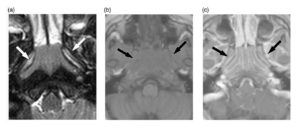

La rinosinusitis micótica (RM) es usalmente clasificada en invasiva y no invasiva. A diferencia de la RM invasiva, la no invasiva se caracteriza por la

DefiniciónLa sinusitis maxilar de origen odontogénico o dental, también conocida como sinusitis crónica de maxilar de origen dental, o sinusitis maxilar odontogénica, es una enfermedad